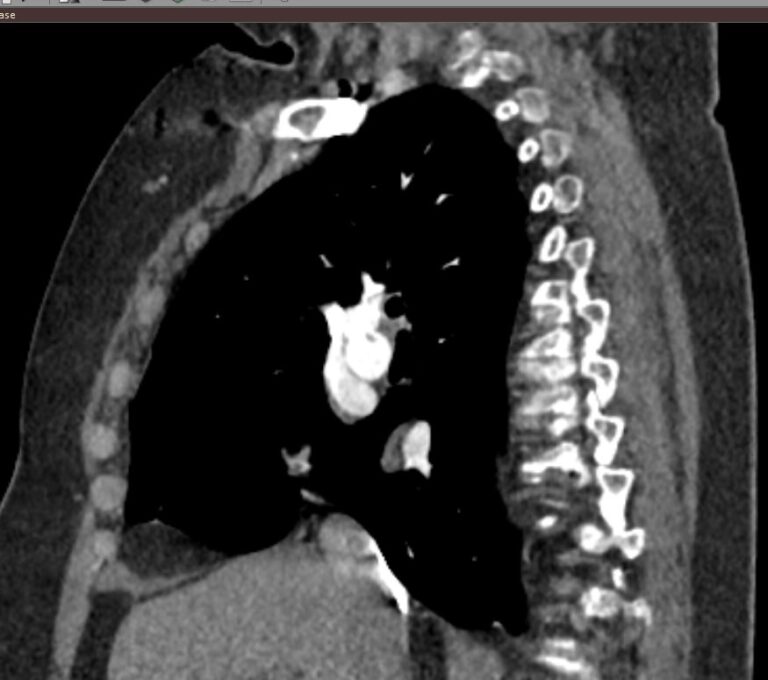

Легочный ствол отходит от правого желудочка сердца, затем разветвляется на правую и левую легочные артерии, которые несут венозную кровь от всего тела к легким для насыщения ее кислородом. Легочные артерии разветвляются на сосуды меньшего калибра, самые мелкие из которых – легочные капилляры – образуют густую сосудистую сеть, где непосредственно происходит обогащение крови кислородом.

Тромбоэмболия легочной артерии характеризуется закупоркой просвета легочной артерии (либо самого легочного ствола, либо более мелких ветвей) тромбом. Тромб может образоваться в глубоких венах нижних конечностей, малого таза, часто после травм, операций, родов, а также в правом предсердии (на фоне нарушений сердечного ритма) и с током крови попадает в систему легочной артерии.

Наиболее информативным, при этом быстрым и неинвазивным (то есть без вмешательства в организм пациента), методом диагностики патологии легочной артерии является мультиспиральная компьютерная томография (КТ-ангиография). Методика основана на использовании рентгеновского излучения в сочетании с цифровой обработкой данных для получения трехмерных изображений сосудистой системы.

Для визуализации кровеносных сосудов в обязательном порядке применяется контрастное усиление. Для этого в вену пациента вводится йодсодержащий контрастный препарат, который попадая в кровоток активно поглощает рентгеновские лучи и ярко контрастирует сосудистую систему, в том числе легочной артерии, на фоне окружающих тканей. Использование контраста дает возможность визуализировать даже мелкие артерии и выявить патологию.

В наших диагностических центрах КТ-ангиография легочной артерии проводится на современных мультиспиральных компьютерных томографах экспертного уровня TOSHIBA AQUILION. Оснащение аппаратов позволяет получать детальные снимки и трехмерные изображения сосудистой системы легочной артерии, при этом применение скоростной мультисрезовой методики сканирования значительно снижает уровень лучевой нагрузки на пациента.